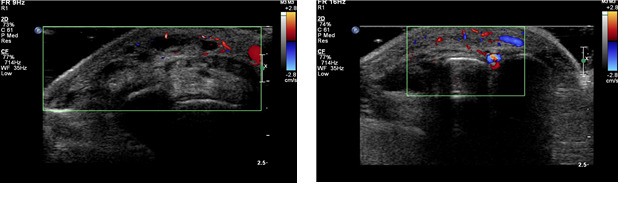

3) 탐촉자로 혈관 확인

- 초음파 기계의 탐촉자를 피부 위에 대고

- 혈관을 따라 천천히 이동

이때 검사자는

- 혈관 두께

- 혈관 내강

- 혈류 속도

- 혈류 방향

을 동시에 본다.

4) 소리로 혈류 확인 (도플러)

- “슈욱―슈욱―” 하는 소리가 들릴 수 있음

- 이게 바로 혈액이 흐르는 소리